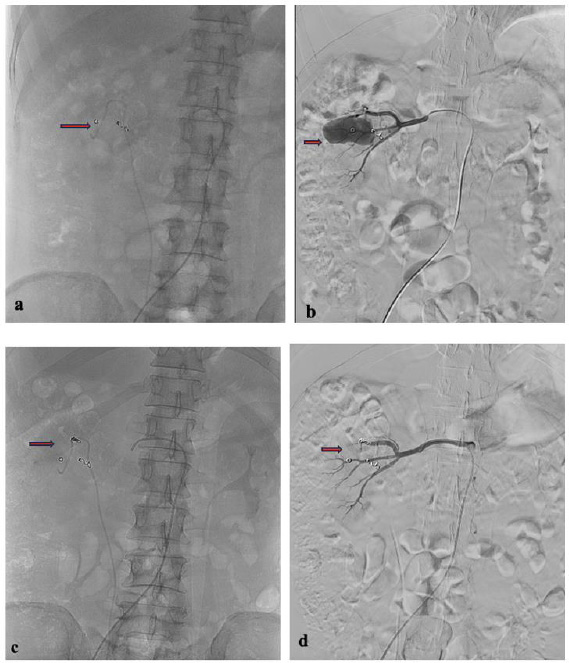

A contrast test was performed that revealed the presence of another pseudoaneurysm. The right renal segmental artery, located in the upper pole of the right kidney, appeared to be the source of the pseudoaneurysm, which the first embolization failed to find or treat. We used 4 mm and 5 mm Coiling Vortx 18 pushable and a PVA 500-710 to target the right renal segmental artery branch and the upper pole of the right kidney. We performed a contrast test and observed significant embolization of the right renal segmental artery, which ultimately resolved the hematuria (Fig. 4). After receiving treatment, the patient's complaints decreased, and hematuria no longer occurred.

Second angiography with a cobra catheter and microcatheter. (a) Coil post first embolization procedure; (b) Pseudoaneurysm of the right renal upper pole segmental artery; (c) Super selective embolization; (d) A contrast test was performed, and the right renal segmental artery was seen to be significantly embolized.